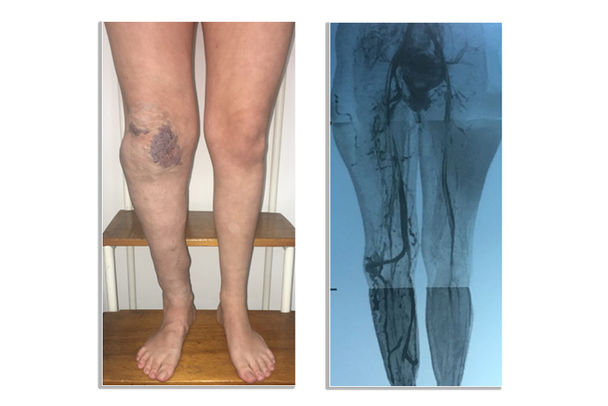

¿QUÉ SON LAS ANOMALÍAS VASCULARES?

Las anomalías vasculares son anormalidades de los vasos que pueden afectar los capilares, las venas, las arterias y los vasos linfáticos, ya sea individualmente o de forma combinada.

Las anomalías vasculares se clasifican ampliamente en dos grupos:

a) tumores que van desde tumores más comunes, como hemangiomas, hasta tumores raros, como hemangioendotelioma kaposiforme;

b) anomalías vasculares: incluida la malformación venosa, así como síndromes combinados, como el síndrome de Klippel-Trenaunay, que implica malformaciones de los capilares, las venas y los vasos linfáticos.